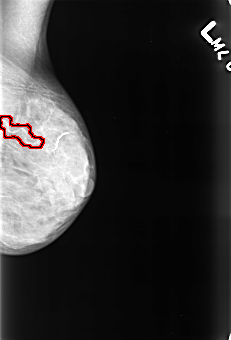

FILE: B_3428_1.LEFT_MLO.OVERLAY

TOTAL_ABNORMALITIES 1

ABNORMALITY 1

LESION_TYPE CALCIFICATION TYPE VASCULAR DISTRIBUTION N/A

ASSESSMENT 2

SUBTLETY 5

PATHOLOGY BENIGN_WITHOUT_CALLBACK

TOTAL_OUTLINES 1

BOUNDARY